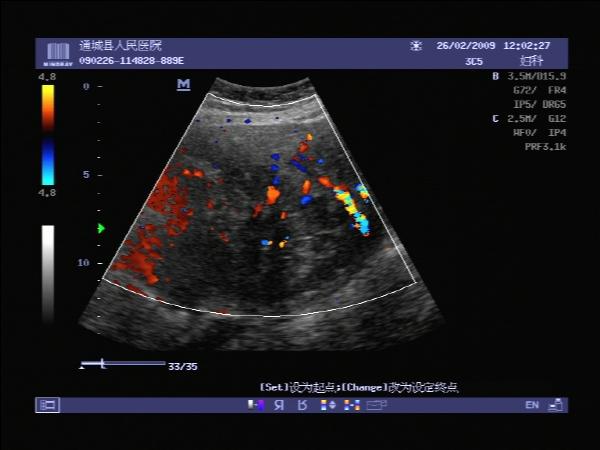

盆腔彩超报告:子宫肌瘤。(或许也漏诊了!)